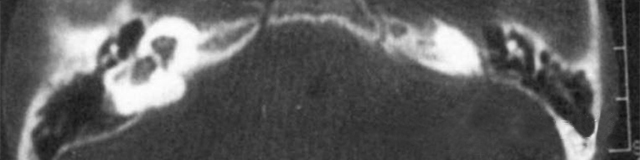

雙側內耳畸形:左側無內耳迷路及內耳道機構,為米歇爾畸形;右側空耳蝸及前庭擴大,為先天性耳蝸畸形

主要依靠顳骨高分辨CT和內耳MRI。

屬常染色體顯性遺傳,是最嚴重的內耳畸形,內耳可完全未發育,可伴有其它器官的畸形和智力障礙。

米歇爾聽障(Michel’s deafness)